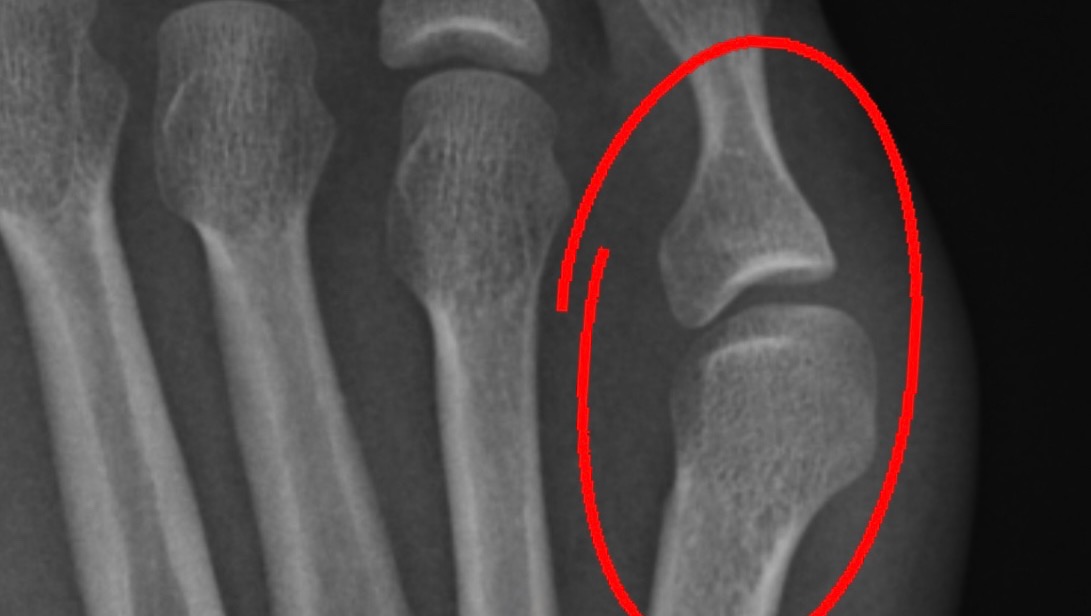

I then began having bouts of disorienting tinnitus, extreme pulling pain behind my eyes, burning & aching neck and head pain that made smashing my head against a brick wall sound like a break from the level of pain I was in. I had an emergency hospital stay after having difficulty walking in mid 2016. Tons of MRIs were done, blood test after blood test, but no doctor could figure it out. I’d nearly pass out from simply standing up or standing up longer than 5 minutes. My feet and legs would turn mottled and purple from blood pooling. Meanwhile, in late 2018 I had to have a hemmorhoidectomy, which is a horribly unpleasant surgery that has one of the most excruciating recoveries. Thanks, pregnancy and hEDS!

Blood pooling from POTS.